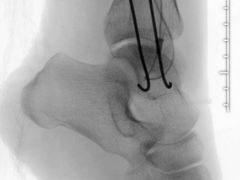

• 上海建工医院